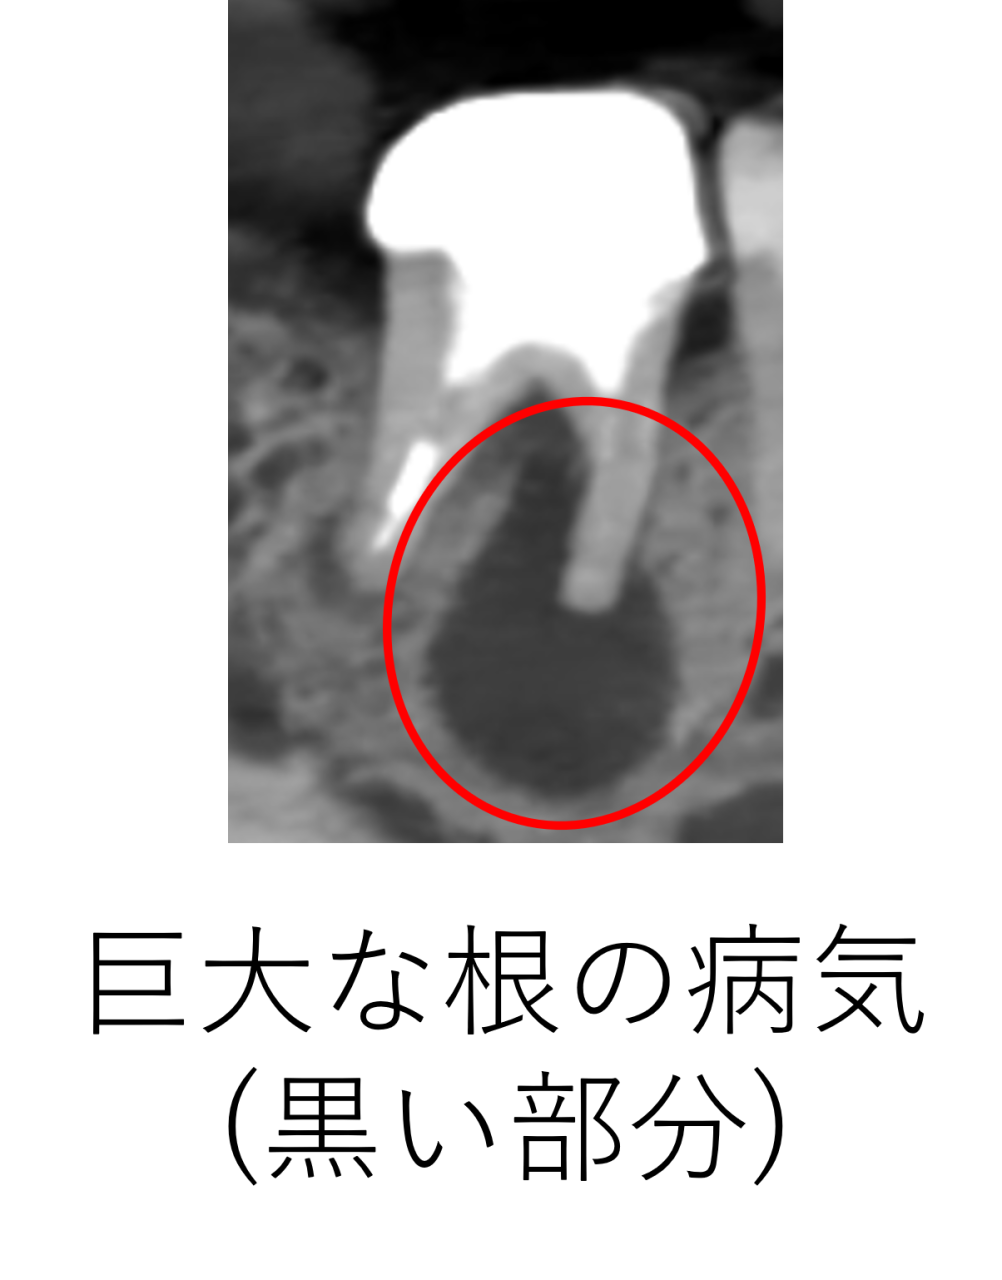

50代の男性患者さんが「右下の奥歯に違和感があり、噛むと鈍い痛みがある」と来院されました。

レントゲンを撮影すると、根の先に広がるような巨大な黒い影が映っていました。これは、歯の内部で取り残された神経が死んで腐って細菌が繁殖し、根の外にまで炎症が広がったことによる根尖病変(膿の袋)です。

この影は骨が溶けてしまった部分を示しており、自然に治ることはありません。放置すると痛みが強くなったり、膿が歯ぐきから出てできものができたりする恐れもあります。